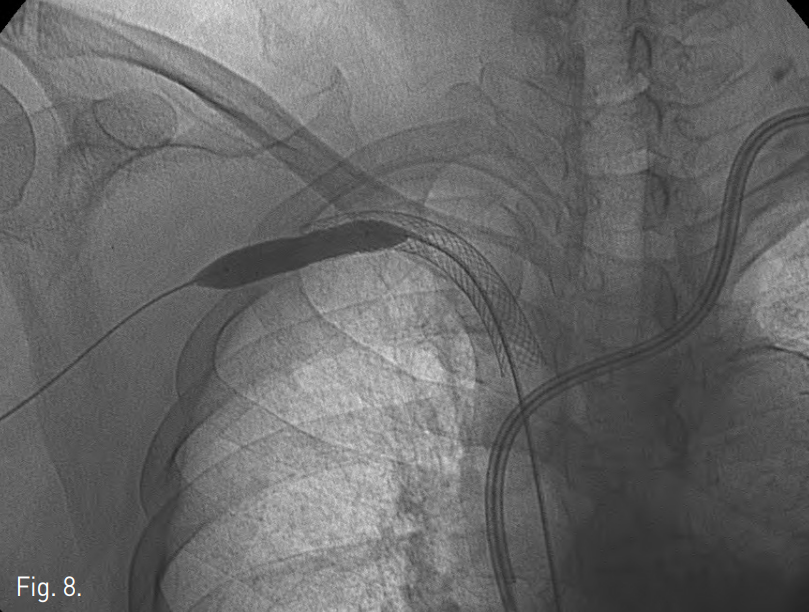

Fig. 4

Radiographs show percutaneously placed guide wire in the SVC, which is pulled out through the femoral access.